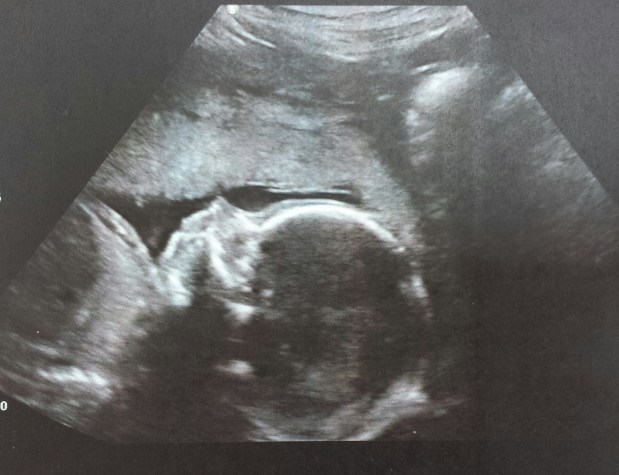

Als Nächstes ging es auf die Liege. Kontaktgel auf den Bauch und auf zur Fips-Rundreise! Der kleine Schlawiner hatte allerdings beschlossen, es uns ein bisschen schwer zu machen: Er lag kopfüber und mit dem Gesicht zur Wirbelsäule gemütlich in meinem Becken – mit der berühmten „Gesichtserkennung“ war es also schon mal nichts. Fetales Nasenbein (das finale Nasenbein bildet sich ja erst später), Gehirn, Augenabstand, Schädelknochen, Oberschenkel, Ärmchen, Wirbelsäule… alles war wunderschön und heil und gesund.

Langes Schütteln, kurzer Sinn: Das Gesicht blieb in Privatbesitz. Lediglich ein Profilbild haben wir bekommen (und sind natürlich beide vollkommen verliebt und unseren Zwerg). Aber ganz ehrlich? Die Geschlechtsumwandlung war aufregend genug – einen direkten Blick in Fips‘ volle Physiognomie hätte mich vollkommen überfordert! Aber ich bin glücklichglücklichglücklich über unser kleines Löwenkind und so geht’s dem weltbesten Fipspapa… es ist alles gut und könnte schöner nicht sein ❤